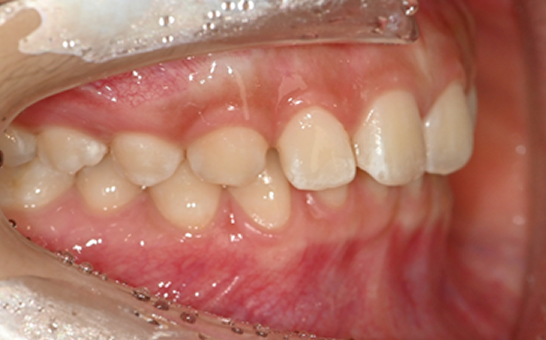

인비절라인 퍼스트(Invisalign First)는 어린이와

성장기 청소년을 위한 투명 교정 장치로, 치아와 턱뼈가

성장하는 과정에 맞춰 설계된 교정 시스템입니다.

해당하는 증상이 있다면 전문의와 상담 후 조기 교정 시

성장기 어린이에게 교합이 틀어지는것을 미리 예방 할 수 있습니다.

앞니의 심한 돌출이나

비대칭으로 인한 기능적

문제가 있는 어린이

※ 바른선택치과의원은 의료법을 준수하며 위 케이스는 실제 내원 환자분의 동의하에 공개된 사진과 동일한 환자분께 같은 조건에서 촬영한 사진을 활용했습니다.

개인에 따라 진료 및 치료 방법이 다르게 적용할 수 있으며, 효과와 부작용이 개인마다 다르게 나타날 수 있는 점을 안내해 드리며, 진료 전 전문의료진과 충분한 상담을 권해드립니다.